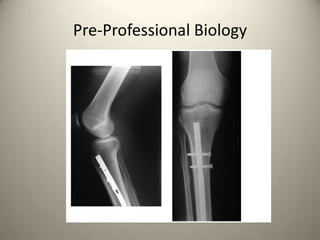

Pre-Professional Biology